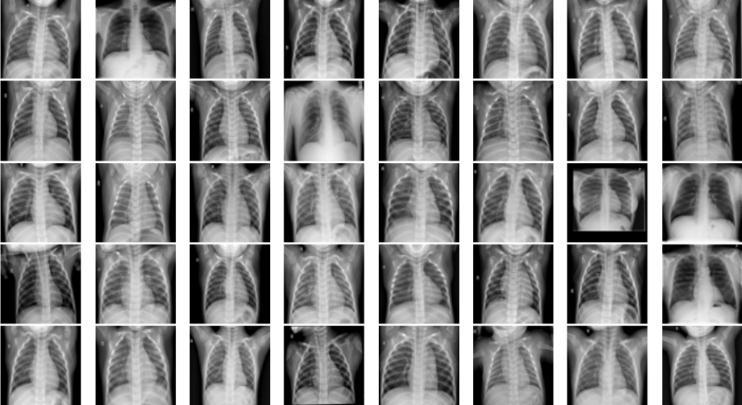

In most cases, the ranges of symptoms of pneumonia andtheCovid 19virusarethesame.Bothareinfectionsof the lungs. Hence, the dataset consists of three separate datasetsofX raysofthechest(COVID 19patients,normal people,andpneumoniapatients).Thereare300photosin all(100COVID 19images,100pneumoniaimagesand100 healthy images). After that, the datasets are divided into two sections: training and testing the classifiers. Fig 1,2,3 showsanexampleofchestX rayimagecollections. Fig.1.

COVIDchestX Rayimages